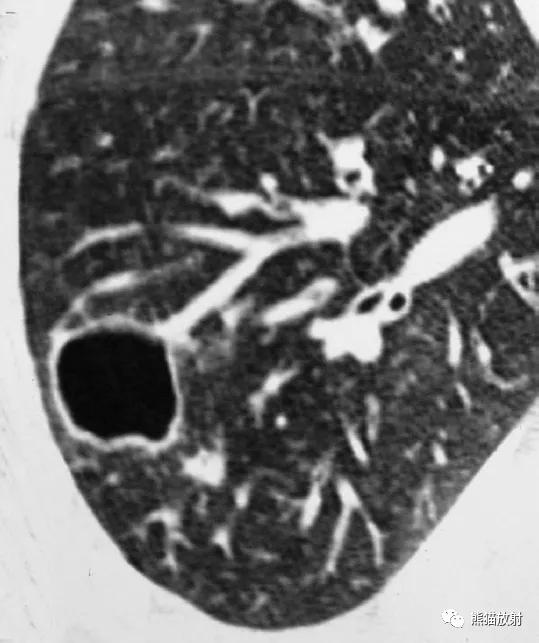

支气管肺炎的特征性CT表现为小叶中心分布的边缘模糊的结节和线样分支影,气腔结节和多灶性小叶范围实变(图)。

↑ 流感嗜血杆菌所致支气管肺炎

48岁男性,咳嗽咳痰,发热。右肺下叶局灶性实变影,边界不清,内见支气管充气征,同时伴有小结节和数个“树芽征”结节。